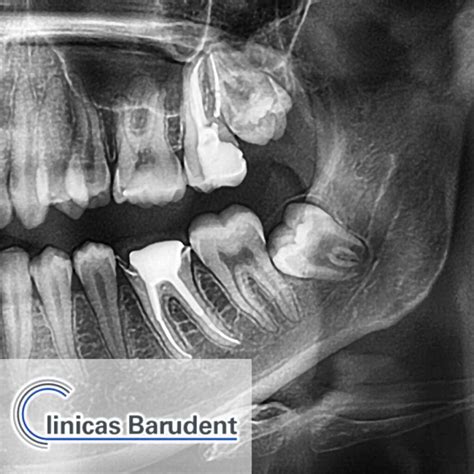

Radiografía dental mostrando la muela del juicio

La muela del juicio es el último diente en erupcionar en la parte posterior de la boca. En la evolución humana, estos molares eran necesarios para masticar alimentos duros y fibrosos; sin embargo, con el paso de los siglos, nuestra dieta ha cambiado y nuestra mandíbula ha reducido su tamaño, dejando poco espacio para estos cuatro dientes finales. A menudo, cuando intentan salir, no encuentran el espacio necesario, lo que provoca que queden atrapadas o impactadas en el hueso o tejido gingival.

Si tu odontólogo determina que la muela del juicio debe ser extraída, el procedimiento suele ser rutinario. Primero, se realiza una radiografía panorámica para observar la posición exacta de las raíces y su relación con el nervio dentario. Durante la cirugía, se utiliza anestesia local para asegurar que el paciente no sienta dolor.

La mejor estrategia es la prevención. Realizarse una radiografía panorámica en la adolescencia tardía permite al dentista predecir el comportamiento de las muelas del juicio. La detección temprana de una erupción problemática puede ahorrar meses de molestias y evitar tratamientos de ortodoncia correctivos posteriores. No esperes a sentir un dolor insoportable para visitar a tu dentista; la salud bucal es un componente esencial de tu bienestar general.